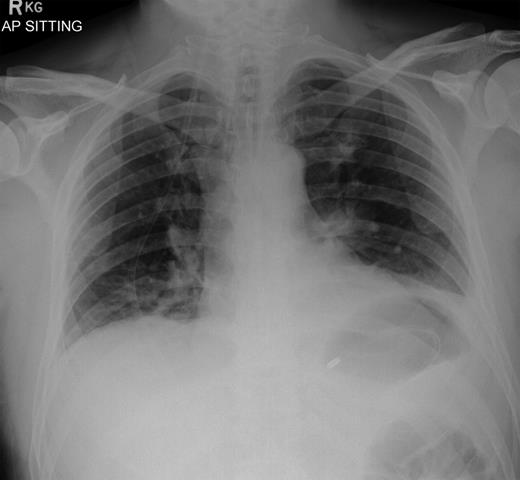

In 2011, a 46-year-old man presented with an acute abdomen. Patient had a 3 day history of abdominal pain with dyspepsia, initially epigastric with pain radiating to his shoulder. He had no associated symptoms of nausea, vomiting or change in bowel habit. There was no history of peptic ulcer disease, inflammatory bowel disease, diverticular disease or malignancy. His pain was refractory to standard analgesics and exacerbated by movement and palpation of the abdomen. There was no past medical or family history of note, and the patient had never experienced these symptoms before. Routine observations were normal, except for tachycardia. On examination, there were no peripheral stigmata of inflammatory bowel disease, abdomen was diffusely tender and tympanic, but soft with normal bowel sounds. Blood tests showed no significant abnormalities, and C-reactive protein (CRP) levels were not measured. Plain abdominal and erect chest radiographs showed pneumoperitoneum (Fig. 1) with Rigler's sign present around small bowel loops lower in the abdomen (Fig. 2).